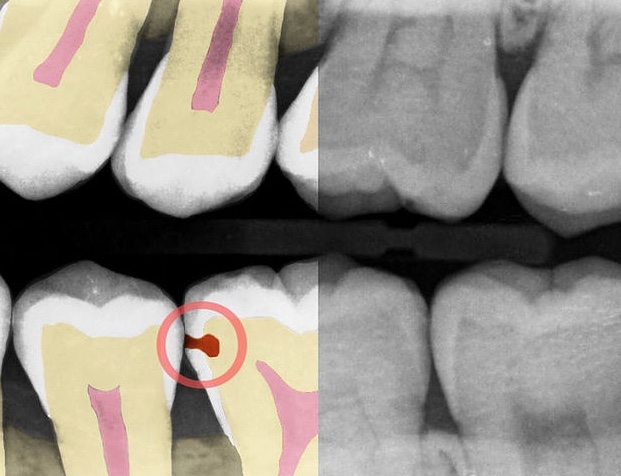

Adra: AI to help dentists find cavities they might otherwise miss. It can also convert fuzzy X-rays into something a bit easier for patients to understand. Currently in a pilot with 20 dentists.